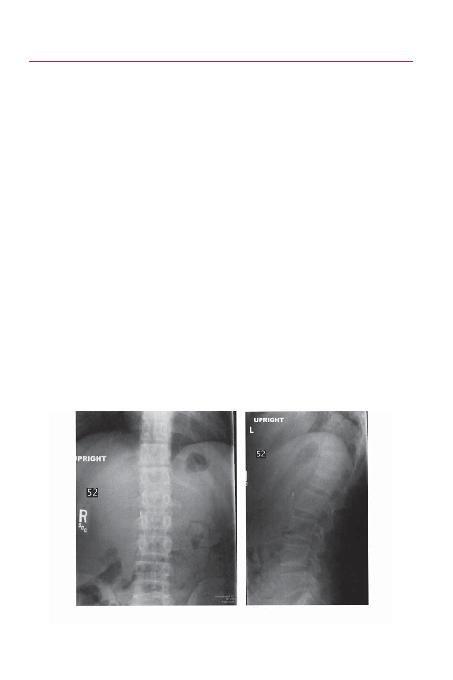

EKL 43-1

Ön arka

(A) ve yan (B) grafilerde L1 kompresyon kiriinin görünümü.

A

B